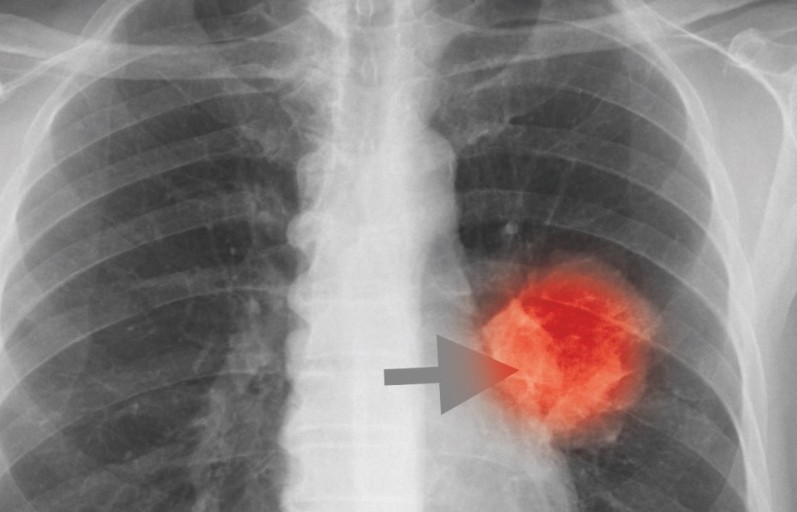

- 호흡 곤란 및 가슴 통증

- 설명: 폐렴의 가장 심각하고 중요한 증상입니다. 폐에 염증이 생겨 폐 기능이 떨어지면서 숨쉬기 힘들어지며, 얕고 빠른 호흡을 하게 됩니다. 심한 경우 가슴에 통증을 느끼거나, 옆구리가 결리는 듯한 느낌을 받을 수 있습니다.